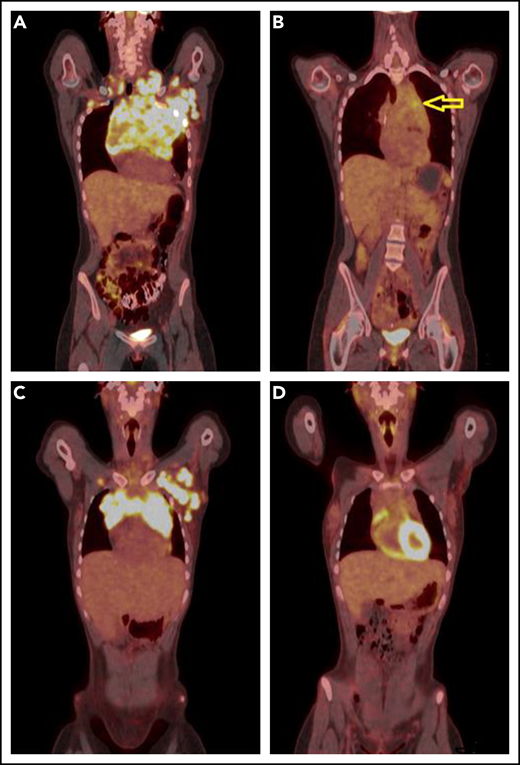

PET-CT’s before and after single agent pembrolizumab. (A) A coronal fused PET-CT image of a 23-year-old woman with cHL shows intensely hypermetabolic bulky lymphadenopathy involving the entire anterior mediastinum, left axillary, bilateral supraclavicular, and subpectoral nodal stations before therapy with pembrolizumab. (B) After 3 cycles of pembrolizumab monotherapy, there was marked anatomic and metabolic improvement of the disease. The residual mass has fluorodeoxyglucose (FDG) activity similar to liver background uptake, with the exception of mild FDG hypermetabolism in the anterior mediastinum (arrow), Deauville 4. (C) A coronal fused PET-CT image of another 23-year-old woman with cHL shows intensely hypermetabolic bulky lymphadenopathy involving the anterior mediastinum and the left axillary and left subpectoral nodal stations with a small right subpectoral lymph node before therapy. (D) After 3 cycles of pembrolizumab monotherapy with CMR, Deauville 3.